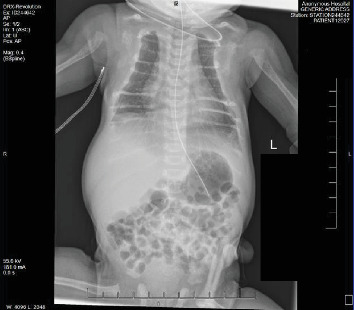

目的:描述一位患有新生儿严重甲状旁腺功能亢进(NSHPT)的女性新生儿的临床表现、诊断挑战和治疗的细节。方法:本病例报告来自回顾性图表回顾。该女婴为近亲父母所生,有多种产前问题,包括妊娠糖尿病、宫内生长受限、羊水过多、产前超声心动图(ECHO)怀疑左心房发育不良。在妊娠37周计划剖腹产后,新生儿表现出中度呼吸窘迫和肋下挛缩。体格检查时,发现颅骨裂、钟形胸部和持续的机械型杂音。结果:出生时的评估显示动脉导管未闭,骨骼结构明显脱矿,肋骨形态不典型。24 h血钙水平升高(14.3 mg/dL),血钙离子升高(2.32 mmol/L), 25-OH维生素D正常(54.2 ng/mL)。一项全面的骨骼调查发现了广泛性骨质减少、干骺端透明和骨折愈合的证据。在43 HOL下重复实验室工作,显示血清钙18.0 mg/dL, iCal 2.67 mmol/L,甲状旁腺激素(PTH)升高2116 pg/mL。NSHPT的诊断基于实验室结果。分子检测证实一个纯合子变异(c.1744T > a;p.Cys582Ser)在钙敏感受体(CaSR)基因中表达,证实了NSHPT的诊断。NSHPT是一种与高死亡率相关的罕见遗传疾病,通常由CaSR基因变异失活引起。患者家族史显示与家族性低钙血症高钙血症(FHH)密切相关,FHH是一种良性疾病,与无症状高钙血症相关,甲状旁腺水平正常至最低限度升高,低钙尿,由CaSR基因杂合失活突变引起。治疗NSHPT通常包括全甲状旁腺或次全甲状旁腺切除术;然而,最初的医疗干预往往是必要的。在此病例中,在成功切除甲状旁腺之前,新生儿接受了降钙素、速尿和静脉输液治疗,以帮助肾脏清除钙。结论:该病例强调了考虑具有复杂临床表现的新生儿罕见遗传疾病的重要性,并肯定了全面咨询和教育的必要性,特别是在近亲父母中,以解决家庭影响并指导适当的干预措施。

Objectives: Describe the details of the clinical presentation, diagnostic challenges, and management of a female neonate with neonatal severe hyperparathyroidism (NSHPT). Methods: This case report was developed from a retrospective chart review. The female infant was born to consanguineous parents-first cousins, with multiple prenatal concerns, including gestational diabetes, intrauterine growth restriction, polyhydramnios, and suspicion of a hypoplastic left atrium on prenatal echocardiogram (ECHO). Following a planned C-section at 37 weeks gestation, the neonate exhibited moderate respiratory distress with subcostal retractions. On physical examination, craniotabes, a bell-shaped chest, and a continuous machinery-type murmur were noted. Results: Evaluation at birth revealed a large Patent Ductus Arteriosus and significant demineralization of skeletal structures with atypical rib morphology. Lab work at 24 h of life (HOL) showed elevated serum calcium level (14.3 mg/dL), ionized calcium-iCal (2.32 mmol/L), and normal 25-OH Vitamin D (54.2 ng/mL). A comprehensive skeletal survey uncovered generalized osteopenia, metaphyseal lucencies, and evidence of healing fractures. Repeat lab work at 43 HOL, showed serum calcium of 18.0 mg/dL, iCal 2.67 mmol/L, and elevated parathyroid hormone (PTH) of 2116 pg/mL. Diagnosis of NSHPT was established based on laboratory findings. Molecular testing confirmed a homozygous variant (c.1744T >A; p.Cys582Ser) in the calcium-sensing receptor (CaSR) gene which confirmed the diagnosis of NSHPT. NSHPT, a rare genetic disorder associated with high mortality rates, is often caused by inactivating CaSR gene variants. The patient's family history revealed a strong correlation with familial hypocalciuric hypercalcemia (FHH), a benign condition associated with asymptomatic hypercalcemia, normal to minimally elevated parathyroid level, and hypocalciuria, it is caused by heterozygous inactivating mutations in the CaSR gene. Treatment of NSHPT typically involves total or subtotal parathyroidectomy; however, initial medical intervention is often necessary. In this case, the neonate underwent medical treatment with calcitonin, furosemide to help facilitate renal clearance of calcium, and intravenous fluids before a successful parathyroidectomy. Conclusions: This case accentuates the importance of considering rare genetic disorders in neonates with complex clinical presentations and affirms the need for comprehensive counseling and education, particularly in consanguineous parents, to address familial implications and guide appropriate interventions.